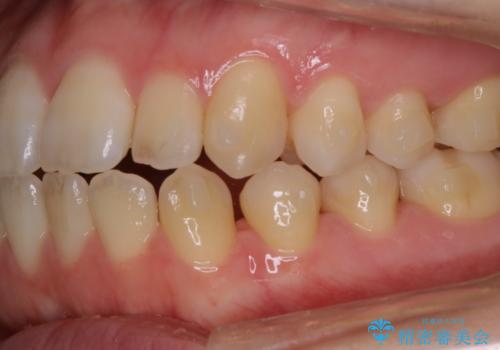

マウスピース矯正インビザライン治療では、歯の表面にアタッチメントという突起を設定します。(アタッチメントは歯の動きを効率的に移動するためのものです)

アタッチメントが歯に付くと、表面が凸凹し磨き残しが多くなったりと、プラークや歯石・着色がつきやすくなることがあります。